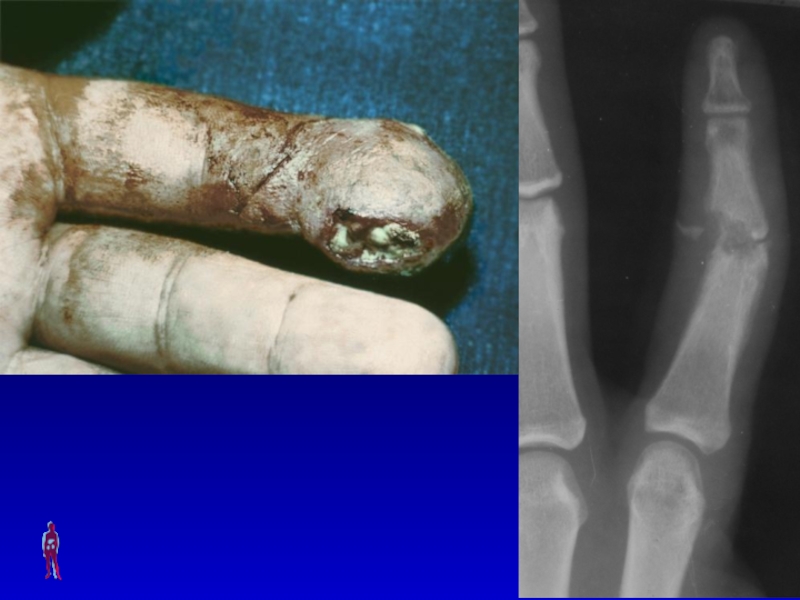

Слайд 70ПАНДАКТИЛИТ

Симптомы: местные (поражение всей толщи тканей пальца) и общие (выраженные

симптомы интоксикации).

Лечение: хирургическое (экзартикуляция пальца в пястно-фаланговом суставе) и консервативная

комплексная терапия.

ПАНДАКТИЛИТСимптомы: местные (поражение всей толщи тканей пальца) и общие (выраженные симптомы интоксикации).Лечение: хирургическое (экзартикуляция пальца в пястно-фаланговом

Слайд 71Пандактилит I пальца правой кисти

Пандактилит I пальца правой кисти